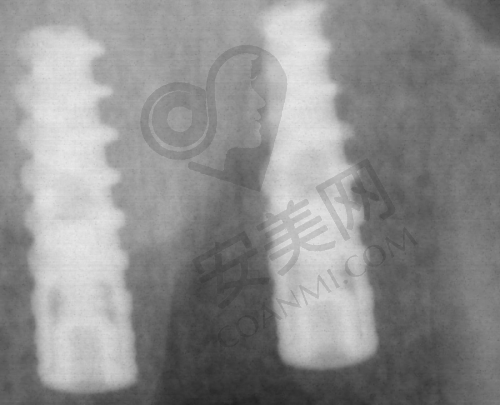

在技术运用上,他善于借助数字化的医疗设备。在种植过程中,这些数字化设备能让种植过程更加科学。比如在确定种植位置时,数字化设备可以提供精细的图像和数据,帮助王弄医生更正确地规划种植方案。而且,这种科学化的种植方式还能实现微创化,减少患者在种植过程中的痛苦和术后的修复时间。

在常规种植方面,王弄医生也有着自己的优势。他会利用数字化设备进行术前评估和方案设计,使种植过程更加精细。而且他的微创种植技术,能让手术创口更小,减少患者的痛苦和术后肿胀的情况。就像有患者缺牙五年不敢种,王弄医生为其设计小创口方案,术后几乎没肿,现在啃排骨都没问题。

对于复杂牙列缺损缺失种植修复,王弄医生更是有着丰富的应对经验。他能够处理各种复杂的口腔情况,如骨量不足等问题。他会采用复杂软硬组织重建手术等方法,为种植创造良好的条件,然后进行种植修复,让患者重新拥有健康的牙齿。